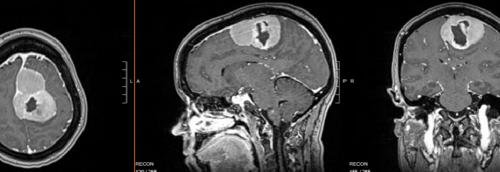

Central nervous system tumors represent the most frequent solid malignancy in the pediatric population. Maximal safe surgical resection is a mainstay of trea...

A 25-year-old male presented with headaches 3 weeks after a car accident. His magnetic resonance imaging images showed a hemorrhagic vermis mass with fourth...